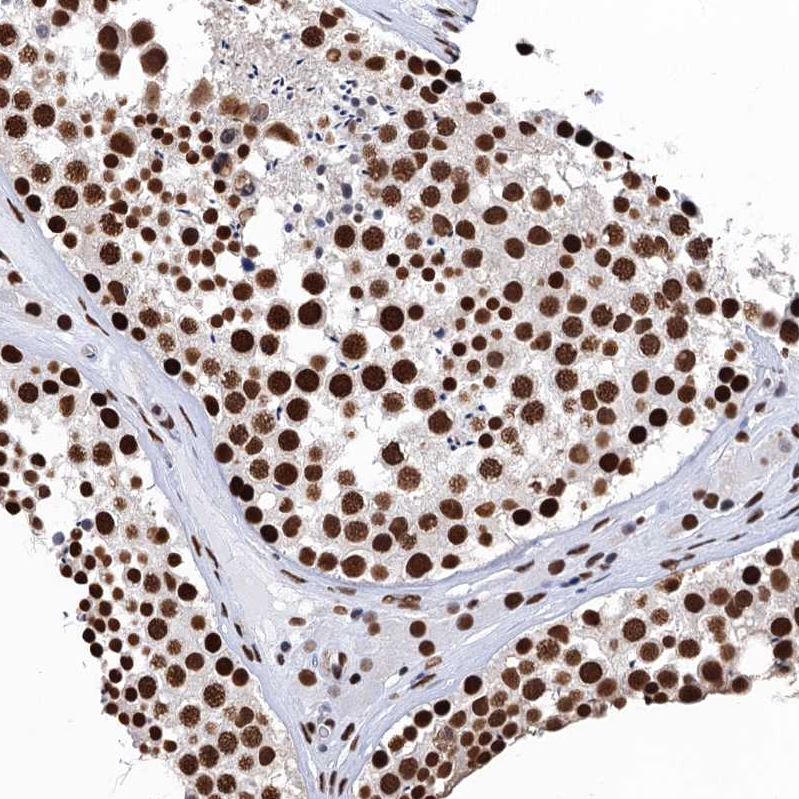

Immunohistochemical staining of human testis shows strong nuclear positivity in cells in seminiferous ducts.